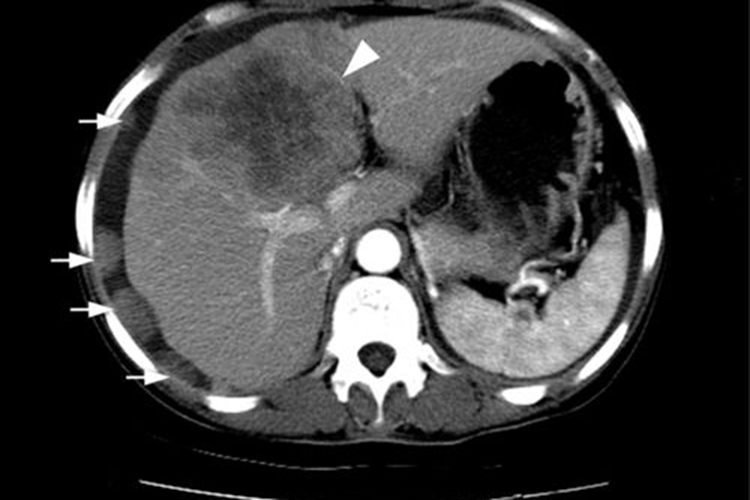

肝癌在CT平扫多表现为低密度影,即肝癌组织比正常组织在图像上暗;随着病灶体积增大,肿瘤组织可发生坏死、出血、钙化或脂肪变性,CT显示肝内密度不均,CT增强可显示动脉期明显强化,静脉期表现为相对低密度。